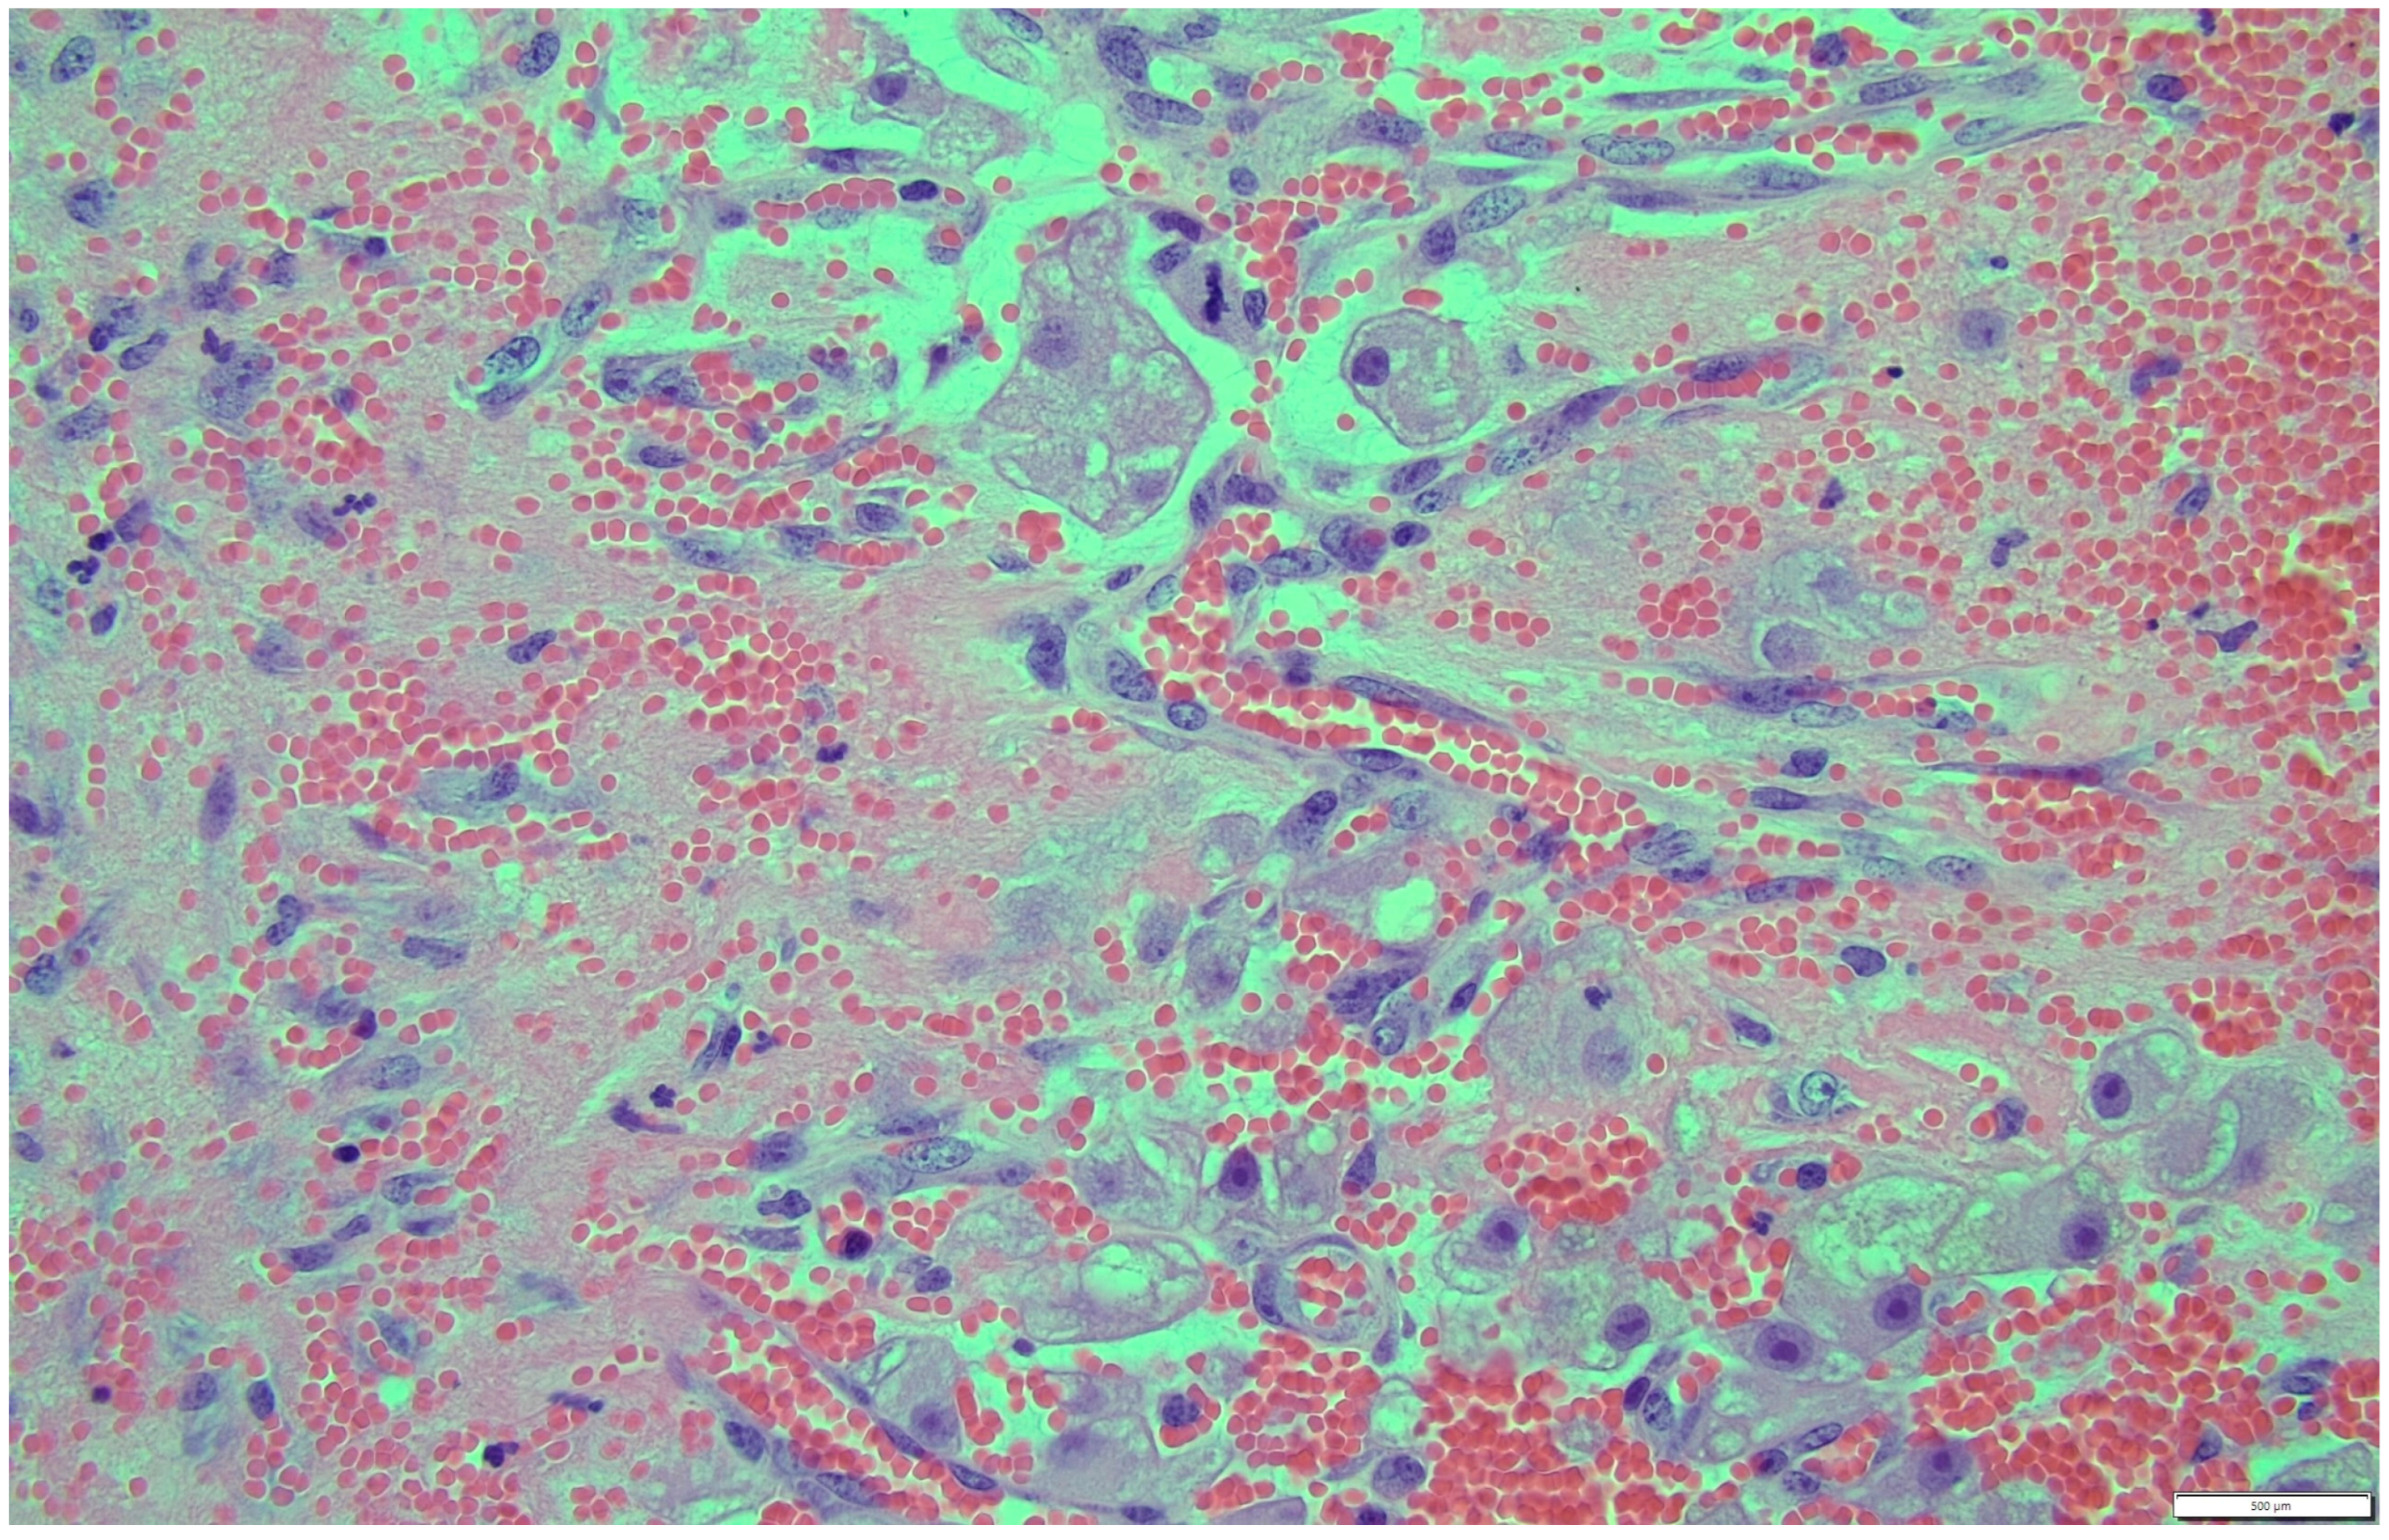

Histologically, both tumor areas were distinctly different from each other (Figure 7 and Figure 8). In the obtained sample for histological examination, the portion of the thecoma was significantly lower (Figure 9). Marked hemorrhage (but not blood-filled lacunae) and very sparse granulation-type connective tissue were observed at the border between both tumor tissues (Figure 10). Hemorrhagic blood masses infiltrated a larger part of the thecoma tissues. A single cystic structure lined with columnar epithelium was found in the hemorrhagic zone, with a very sparse amount of mucus-like material in the lumen (Figure 11).

Figure 10. Marked hemorrhage (but not blood-filled lacune) and very sparse granulation-type connective tissue were observed at the border between both tumor tissues. HE, 200× magnification.